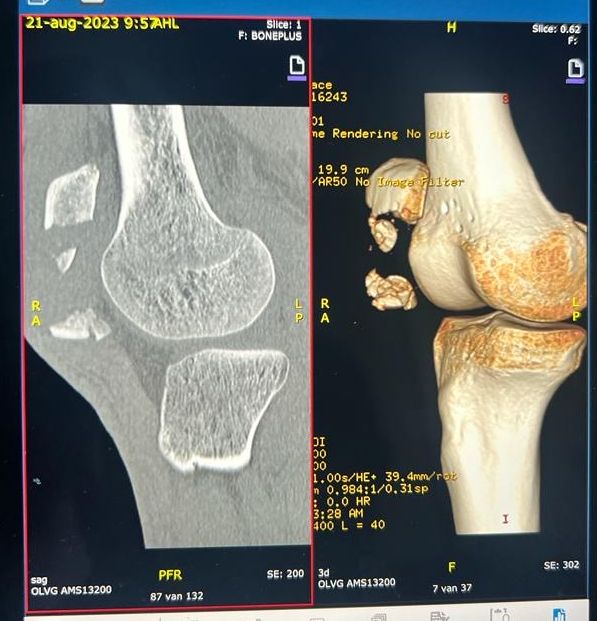

Like his race season, Gloag’s kneecap was in bits

Half of the distal pole of his right kneecap was shattered, meaning his leg had to be immobilised in a straight cast for six weeks to allow the bone to heal. “I had complete knee reconstruction surgery where they put a fair few pieces of metal into the kneecap to help join the gap between the top and the bottom half,” he says. “Luckily when you’re fit, healthy and [when] young the body heals remarkably well.” It was forced inactivity caused by the cast, rather than the broken bone, that proved more difficult to recover from. “After 48 hours of no movement, the quads start to atrophy,” says Gloag, explaining how unused muscle essentially stops functioning. After two weeks, the cast was temporarily removed to enable him to take that shower. “It was one of the strangest moments of my life,” he says. There followed another four weeks in the cast and further wasting of the leg. “My muscles had atrophied so much that it was basically just bone at that point.”